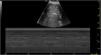

We report the case of a 53-year-old woman admitted to the intensive care unit (ICU) due to bilateral intraparenchymal hemorrhage requiring mechanical ventilation. Following the insertion of a nasogastric tube, the hepatic ultrasound reveals the presence of multiple heterogeneous hyperechoic images (Fig. 1). Microbubbles were also identified, on M-mode, in the portal vein and its visible branches (Fig. 2). A follow-up ultrasound performed 8h later confirmed the disappearance of all these findings (Fig. 3).

These events are indicative of aerobilia due to the infusion of air for epigastric region auscultation of the correct placement of the nasogastric tube, which is probably in the duodenum with an incompetent papilla.